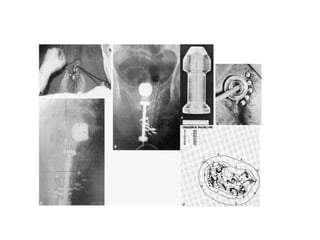

Postoperative brachytherapy (Intravaginal radiotherapy)

Intravaginal radiotherapy (IVRT)

Female urethral cancer